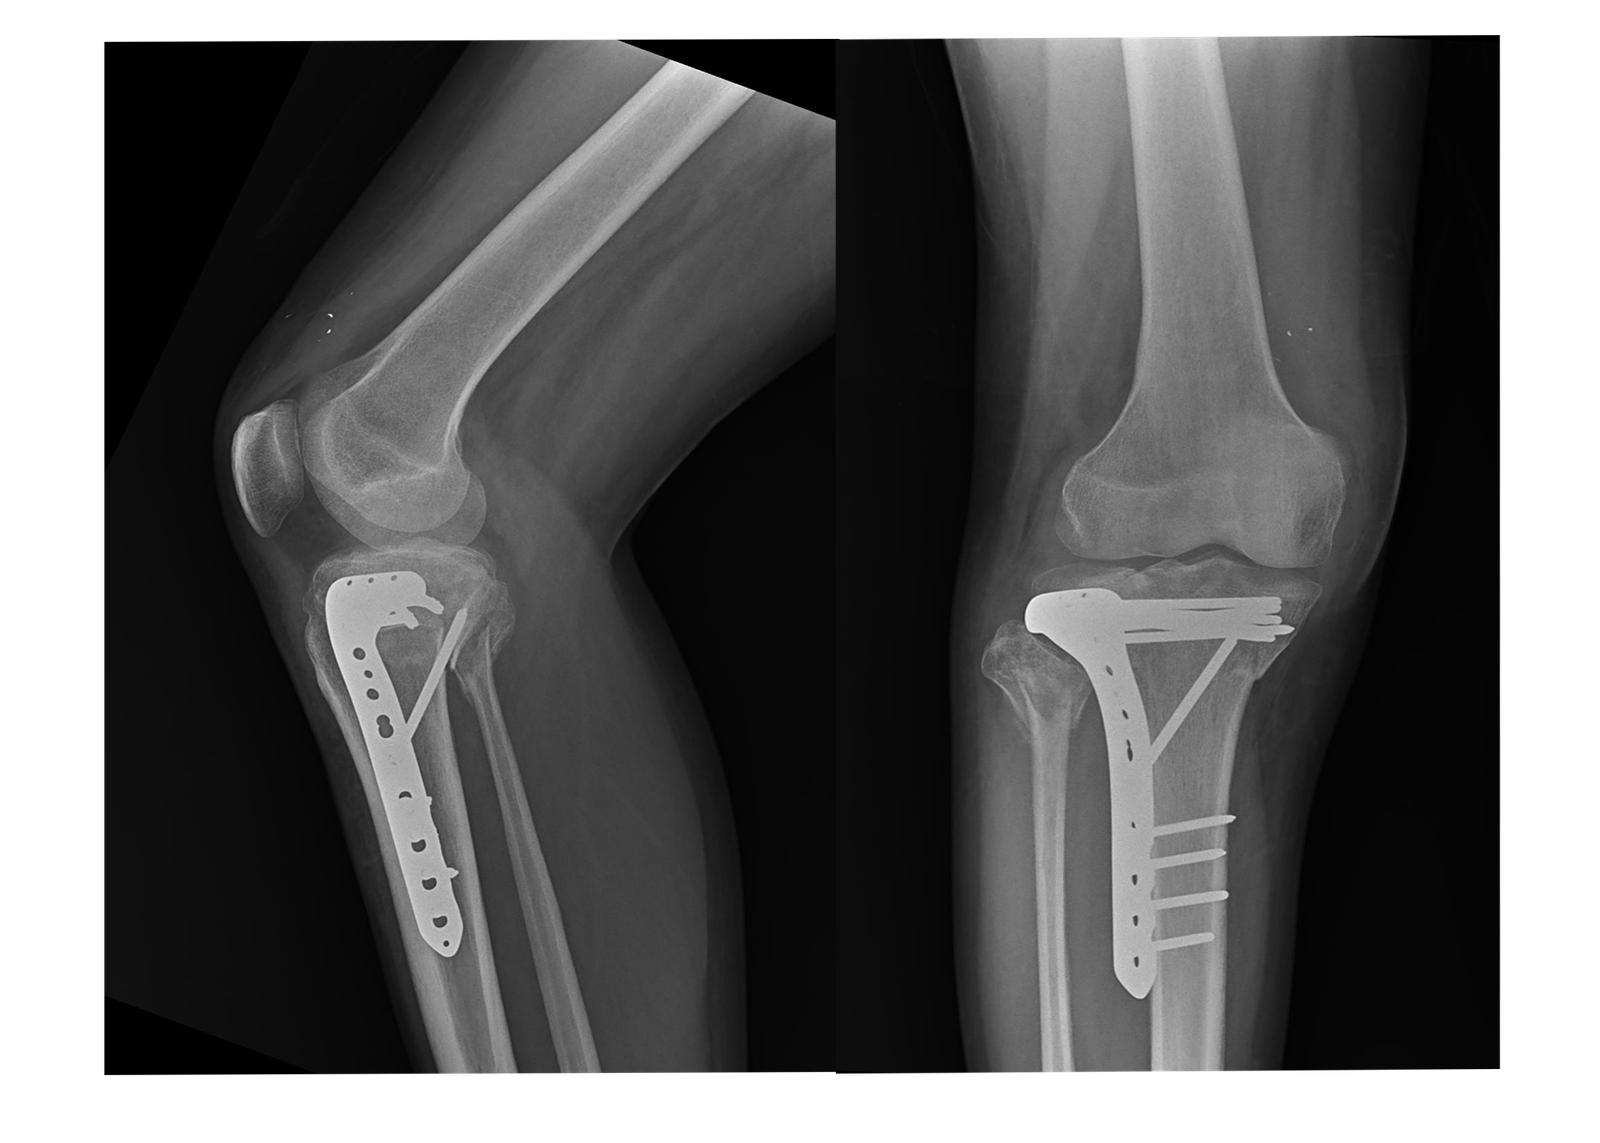

1. Total Knee Replacement (TKR):

Our Total Knee Replacement procedures are designed to relieve pain and restore function in patients suffering from severe arthritis or knee damage. Using advanced surgical techniques and high-quality prosthetic implants, we ensure that patients receive the best possible care and achieve optimal recovery.